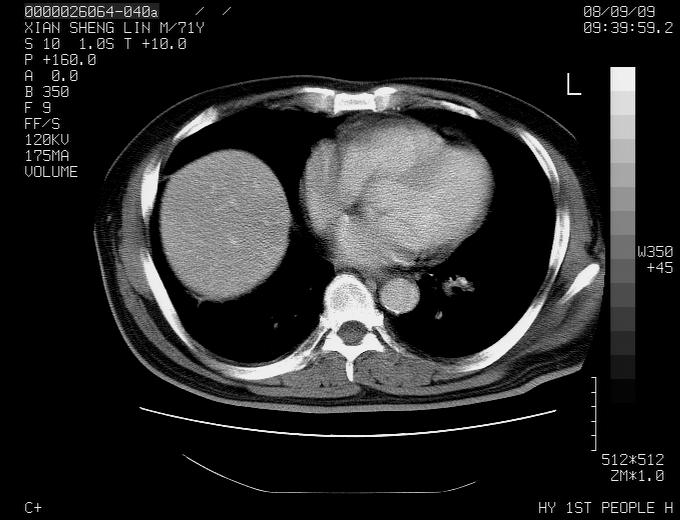

标题: CT15869:男性,71岁,因咳嗽而就诊,请讨论右上肺病变性质 [打印本页]

患者,男性,71岁,因咳嗽而就诊,

典型的右肺中心性肺癌并纵隔淋巴结转移

病灶中等程度强化 还是支持肺癌诊断

考虑右肺中心性肺癌并右肺门及纵隔淋巴结转移。

1,右肺中心型ca,气管隆突旁淋巴结转移。

2,右膈明显抬高,建议肝脏扫描排除转移或原发灶。